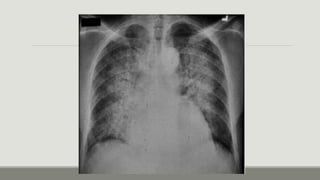

Rx de tórax

Fase

alveolar:

Patrones alveolares mal definidos, confluentes, con

distribución parcheada, bordes irregulares y

predominante en el tercio interno del pulmón,

patrón en ¨alas de mariposa’ (la consolidación se

extiende desde la región perhiliar hacia afuera,

dejando no daño a la zona subpleural)

Rx de tórax Fase alveolar: Patronesalveolares mal definidos, confluentes, con distribución parcheada, bordes irregulares y predominante en el tercio interno del pulmón, patrón en ¨alas de mariposa’ (la consolidación se extiende desde la región perhiliar hacia afuera, dejando no daño a la zona subpleural)